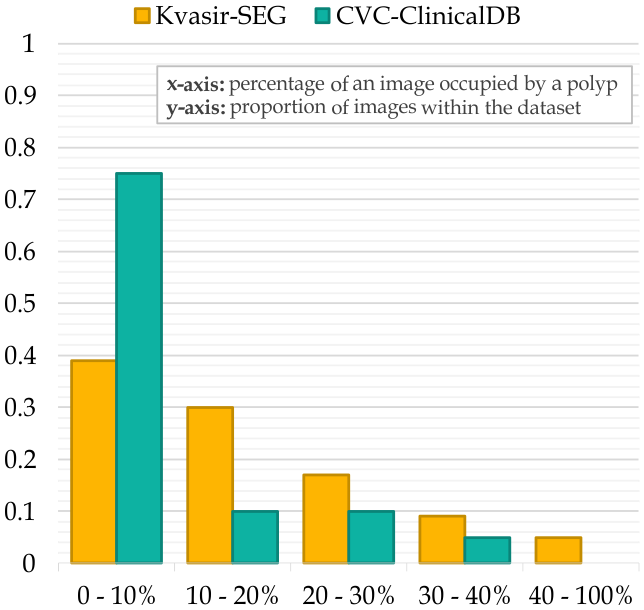

Automated gastrointestinal polyp segmentation presents significant challenges due to various factors illustrated in Fig. 1(b). Uneven illumination from body fluid reflection can degrade image quality, while noise artifacts like surgical instruments and intestinal contents complicate segmentation. Low contrast between tissues hinders accurate polyp localization and identification. Additionally, residual stool and digestive fluids can obscure internal tissues, making differentiation difficult. Polyp boundaries are blurred or unclear due to similar appearance patterns. Furthermore, inter-patient variability and diverse polyp types exhibit various colors and textures. Moreover, an imbalance in pixel distribution, as shown in Fig. 1(c), with the background area often exceeding the polyp area, introduces noise that affects segmentation performance.